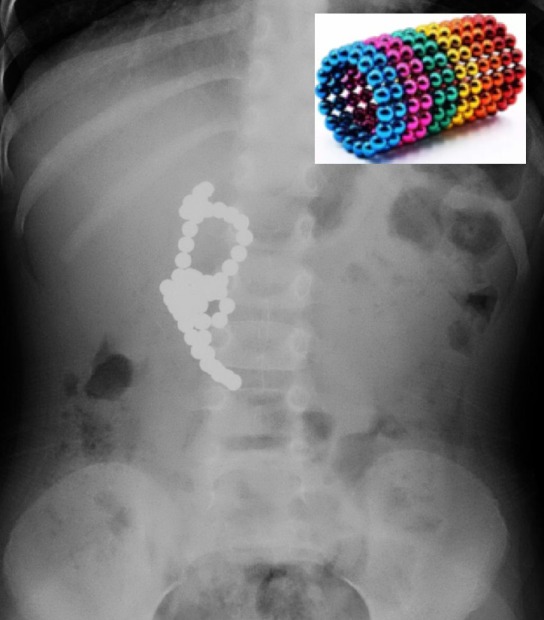

Doctors extracted 51 small ball magnets from the three-year-old’s stomach

“An X-ray revealed several magnets inside her stomach.

“The child had swallowed 51 such pieces – small magnets that are ball-like parts of toys.”